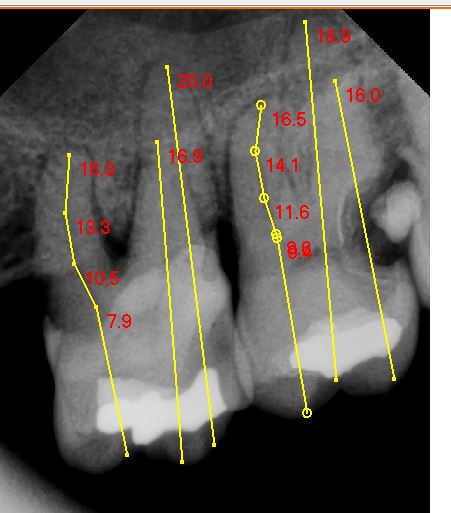

PERIAPICAL PLUS

PERIAPICAL DIGITAL

SERIE PERIAPICAL